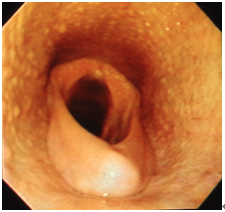

DDSP(軟口蓋背方変位)

軟口蓋が喉頭蓋の背方(上方)へ変位する疾病です(図3)。変位によって、一時的な閉塞が起こったり咽喉頭部での乱気流が作り出されたりするため、パフォーマンスが大きく低下します。調教時に「ゴロゴロ」という呼吸音が聞こえるのが特徴です。安静時の内視鏡検査では、喉頭蓋が薄い以外ではほとんど異常所見がみられないことが多いようです。多くは運動時に症状が出るため、運動時内視鏡検査によって診断を行います。また、舌縛りや8の字鼻革の使用により、症状が解消することがあります。さらに喉頭蓋が非常に薄い場合もDDSPを発症しやすくなりますが、年齢とともに喉頭蓋が成長して症状を見せなくなります。治療は軟口蓋をレーザーで焼絡する方法や、Tie-forwardと呼ばれる甲状軟骨を底舌骨へ縫合する方法があります。

3_13

図3 DDSP(軟口蓋背方変位)